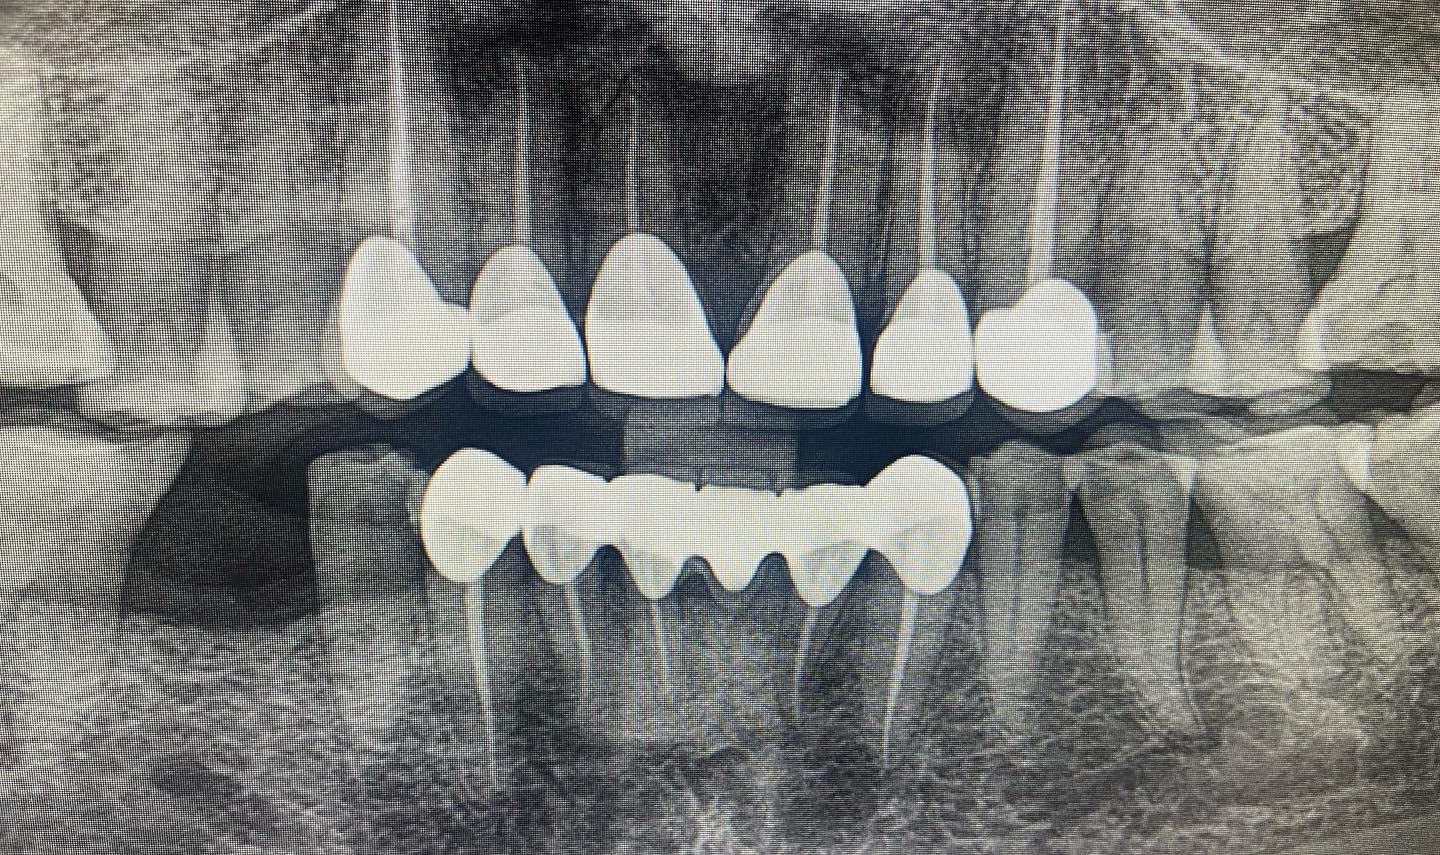

Dental X-ray is a cornerstone of effective dental care. They provide invaluable insights into your oral health that are not visible during a standard examination. Here’s why dental X-rays in Kolkata, West Bengal are crucial: Accurate Diagnosis: Dental X-ray images reveal detailed views of your teeth, bones, and surrounding tissues, allowing us to detect issues such as cavities, infections, or bone loss that may not be visible during a physical exam. Treatment Planning: With precise dental X-ray imaging, we can plan your treatment effectively, ensuring that any procedures are tailored to your specific needs and that no underlying issues are overlooked. Ongoing Monitoring: Regular dental X-rays in West Bengal help track the progress of existing conditions, monitor new issues, and assess the success of previous treatments. You can also know about 3D INTRA-ORAL SCANNING

At Dentasia, we offer a range of dental X-ray in Kolkata, West Bengal services to meet all your diagnostic needs. Each type of dental X-ray provides different insights into your oral health: Teeth X-Ray/RVG: Also known as Radiovisiography (RVG), this teeth X-ray focuses on individual teeth and their immediate surroundings. It is ideal for detecting issues such as decay, root problems, and infections. Bitewing X-Rays: These dental X-rays show the upper and lower teeth in a specific area of the mouth. They are particularly effective for identifying cavities between teeth and assessing the level of bone support around your teeth. Panoramic Dental Imaging/OPG: This dental X-ray in West Bengal captures a broad view of your entire mouth, including all teeth, jaws, and surrounding structures. It is useful for evaluating overall dental health, planning orthodontic treatment, and detecting issues like impacted teeth or jaw disorders. You can also read about How long do dental implants last ? here CBCT (Cone Beam Computed Tomography): CBCT provides three-dimensional imaging of your teeth, jaws, and surrounding anatomy. This advanced dental X-ray technique is essential for detailed assessments required for complex cases such as implant planning, bone structure evaluation, and precise orthodontic treatment.